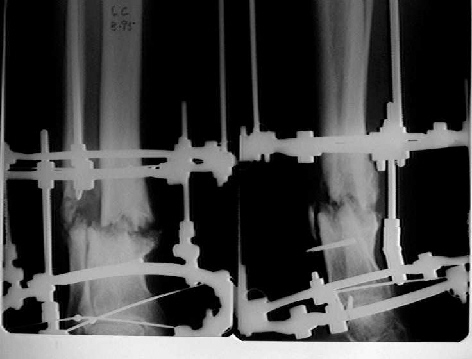

It seem a stiff pseudarthrosis. I will do a axial correction and lengthening if necessary with Ilizarov frame without any corticotomy. Probability of success will be 100% and relapse of infection 0%. You can see one case attached.